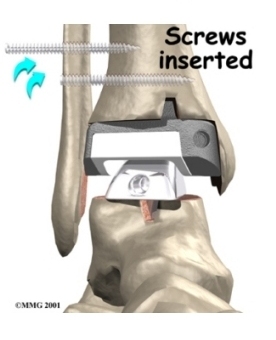

Each artificial ankle prosthesis is made of two parts:

- The tibial component is the part of the artificial joint that replaces the socket portion of the ankle (the top section).

- The talus component replaces the top of the talus.

The tibial component is usually made up of two parts: a flat metal piece called a metal tray that is attached directly to the tibia bone, and a plastic cup that fits onto the metal piece, forming a socket for the artificial ankle joint. The talus component is made of metal and fits into the socket of the tibial component.

Your surgeon may use a special type of epoxy cement to attach the metal components to the bone. This is called a .

Some surgeons prefer to put the new joint in without using cement. This is called an . The surface of this type of prosthesis bears a fine mesh of holes that allow bone to grow into the mesh and attach the prosthesis to the bone.